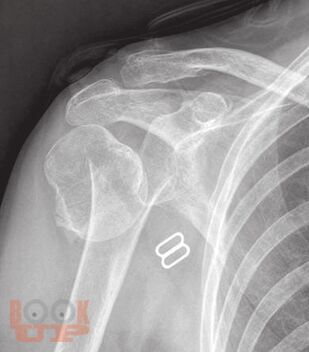

В пособии рассматриваются различные заболевания и травмы конечностей в аспекте их выявления лучевыми методами. Пособие составлено с учетом комплексного подхода к патологиям (костей и мягких тканей, суставов, сосудов, нервов) и диагностических методов (классического рентгеновского, КТ, МРТ, ультразвукового).